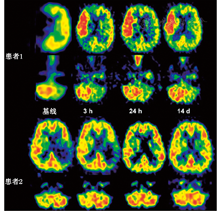

1.脑缺血病灶的检测。SPECT脑灌注显像及PET的血流和代谢研究[27,28]可探查缺血部位及缺血病灶的范围,这2种技术在检测梗死发生时间和梗死范围方面均比CT更为灵敏。在脑卒中发生后的第1个8小时,SPECT检测结果阳性率为90%,灵敏度为61%~74%,特异性为88%~98%[29]。早期PET研究显示,局部缺血部位存在血流和葡萄糖摄取差异,表明存在无氧糖酵解[30],测定氧摄取分数(oxygen extraction fraction, OEF)可使研究人员在梗死发生后的48 h内继续监测梗死的进展情况[31]。在此期间,增加灌注可观察到组织的不可逆损害,称为过度灌注[32];后期在梗死灶中心及周边区域可观察到相对充血(图1)。短暂性脑缺血发作可区别于缺血性卒中而发生在出现症状后的6 h内,SPECT在病侧的计数率为对侧的70%(脑卒中组织灌注值为对侧的35%~60%)[33];PET在病灶部位的CBF显著降低,但OEF增加[34]。

脑卒中早期,PET研究[40,41,42,43]发现脑缺血区域由不同的组织构成。测量时(通常在脑卒中发生后的几个小时)rCBF低于12 ml·100 g-1·min-1的组织或CMRO2低于65 mmol·100 g-1·min-1的局部区域在后期CT扫描中被发现是梗死区域。缺血区域残存的CMRO2是神经元相对完整的一个指标,预示该区域CBF将减少至12~22 ml·100 g-1·min-1。这种不完全的缺血灌注模式[41]是一个缺血半暗带,该区域的OEF增加(由正常值40%上升到80%)。PET研究将缺血区域分为3个部分:缺血核心区(12 ml·100 g-1·min-1),通常呈现出坏死;缺血半暗带区(12~22 ml·100 g-1·min-1),是仍然存活的组织,但可能发生梗死,也可能恢复功能;低灌注区(22 ml·100 g-1·min-1),没有受到血液供应不足的明显损害(图2)。缺血半暗带的进展及转化为梗死是一个动态过程,不可逆损伤的发生也是从缺血中心向周边进展。PET可对这个病理进展过程进行跟踪,并对动物模型和急性脑卒中患者的生理变量进行研究[44,45,46](图2)。

急性缺血性脑卒中的疗效监测也是建立在显像研究的基础上,缺血半暗带再灌注后可改善神经功能的损害(图5):患者接受rtPA治疗后的再灌注量与对照组相比显著增加[64]。在脑卒中发病后的3 h内,H215O PET CBF显像能够确定再灌注可修复组织的容积,并与梗死3周后MRI的梗死容积对比[65]。最初缺血的区域(即血流量低于阈值12 ml·100 g-1·min-1)再灌注后血灌注量接近正常水平,并预测在3周内临床症状得到明显改善。在一个12例的小样本研究中,灌注量低于脑卒中临界值的灰质,仅22.7%在溶栓治疗后会发生坏死,这意味着有很大一部分缺血组织再灌注治疗后仍可修复。另一个11例患者的PET研究[66]发现,只有当11C-氟马西尼在皮质摄取不减少或不低于白质平均摄取值的3.4倍时,缺血组织的再灌注才有效。这种神经元完整性的标志物可作为不适宜接受治疗的不可逆损伤组织的一个指标。

缺血性脑卒中病灶的早期PET研究[30]发现,其代谢和血流量减少的范围超过其受损组织形态学改变的范围,这与SPECT显像发现类似。最显著的表现是病灶对侧小脑的脑血流减少和代谢减低,称为交叉性小脑失联络[84],在脑卒中患者立即出现,在涉及小脑-皮质-脑桥途径而又成功地再灌注治疗的可逆性病变中持续存在(图5)[85]。交叉性小脑失联络是由一些神经元介导的效应,且因急性缺血而失活的部位已被证明位于小脑[86]。另外,在同侧皮质和基底神经节也存在脑血流的减少和代谢减低,但由于选择性的神经元缺失或血液供应不足也会影响到这些区域,故具体原因不明。然而,在非缺血性病变(如脑肿瘤和颅内血肿)中也会出现这种效应,因此相对于原发灶性质为何,其似乎与病变发生部位关系更为密切[84]。在皮质和皮质下病变中,顶叶和额叶梗死通常引起同侧基底节和对侧小脑的脑血流减少和代谢减低。该效应可通过皮质-脑桥-小脑途径损伤来解释。基底神经节的梗死可引起同侧大脑及对侧小脑失活。丘脑梗死主要影响病侧皮质,只有病变累及内囊时才会出现明显的小脑失活[87]。脑干和小脑梗死通常不引起前脑结构的不对称失活。交叉失联络不能通过常规的PWI参数检测到。临床症状可通过病灶远处的改变来解释,交叉失联络的程度与临床功能的缺损程度(脑卒中评分量表评估)与之后的功能恢复程度相关[88]。脑功能网络特定区域的失活和再激活在临床症状的出现和恢复中发挥着重要作用。